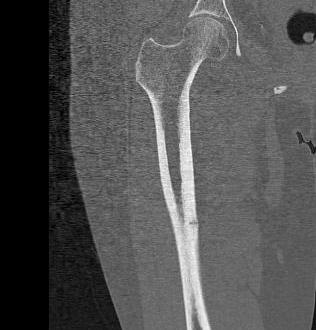

Atypical femoral fracture related to bisphosphonates

- reports of atraumatic bilateral femoral fracture

- seen in women taking bisphosphonates for more than 5 years

- insufficiency fracture

- characterised by short oblique subtrochanteric and diaphyseal fractures

- typically see lateral cortical thickening / sclerosis / beaking before the fracture

- must check contralateral femur if have a fracture

- xray any patient complaining of thigh pain

- recommend drug holidays to prevent this complication